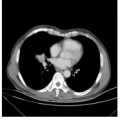

男, 56岁 于外院住院抗炎治疗,行支气管镜检查示:右肺中叶支气管内肿物,病理回报为腺癌。为进一步诊治来我院。辅助检查:气管镜(外院):右肺中叶外侧段开口处肿物。影像学:肺CT示双肺炎,右肺占位性病变。临床诊断:右肺癌,行右肺中叶叶切除术。 |

| 影像学检查:(点击查看大图) |